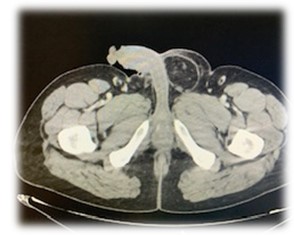

Caso 1: se solicita un TC abdominal: Hernia inguinal indirecta izquierda, de contenido graso, sin signos de complicación. Se programa de forma prioritaria la intervención de Hernia inguinoescrotal izquierda H3F1.